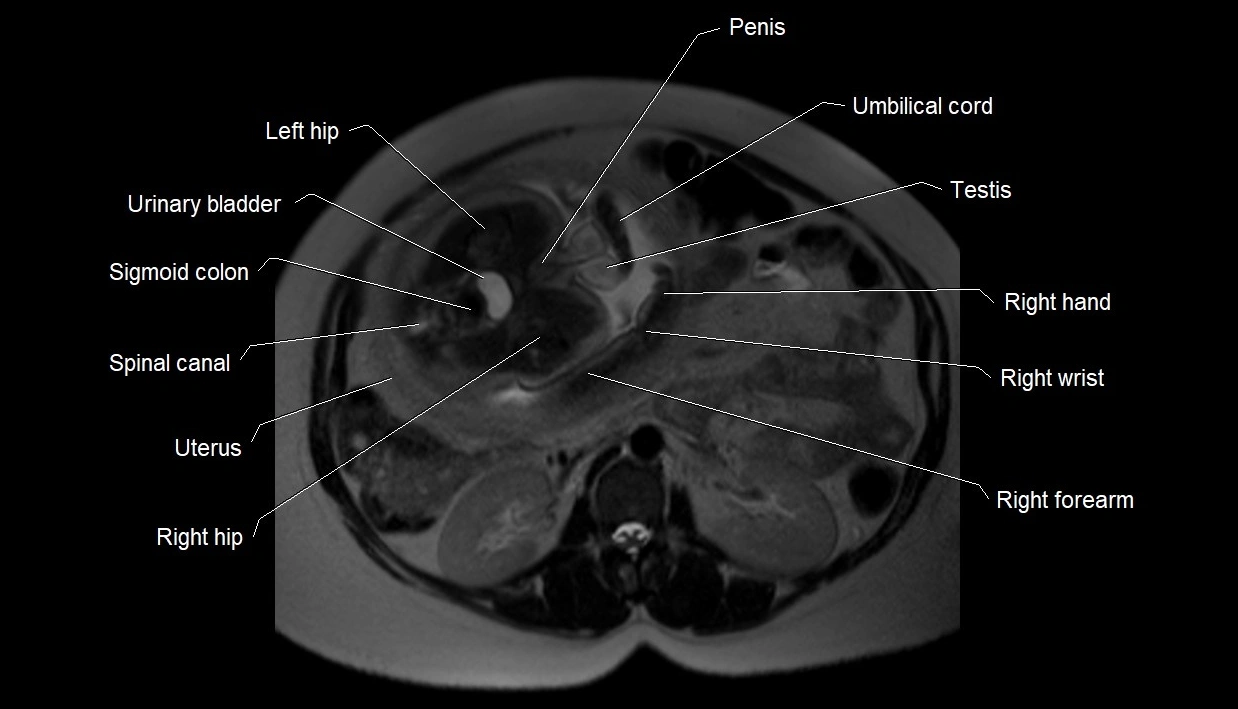

MRI Appearance

T2 HASTE (T2 GRE):

• Amniotic fluid shows very bright hyperintense signal

• Provides natural contrast against fetus and placenta

• Small particles (vernix) may appear as scattered hypointense foci within bright fluid

T1 GRE:

• Amniotic fluid shows low signal intensity (dark)

• Hemorrhage, infection, or proteinaceous content may cause focal or diffuse high signal intensity

MRI image

image